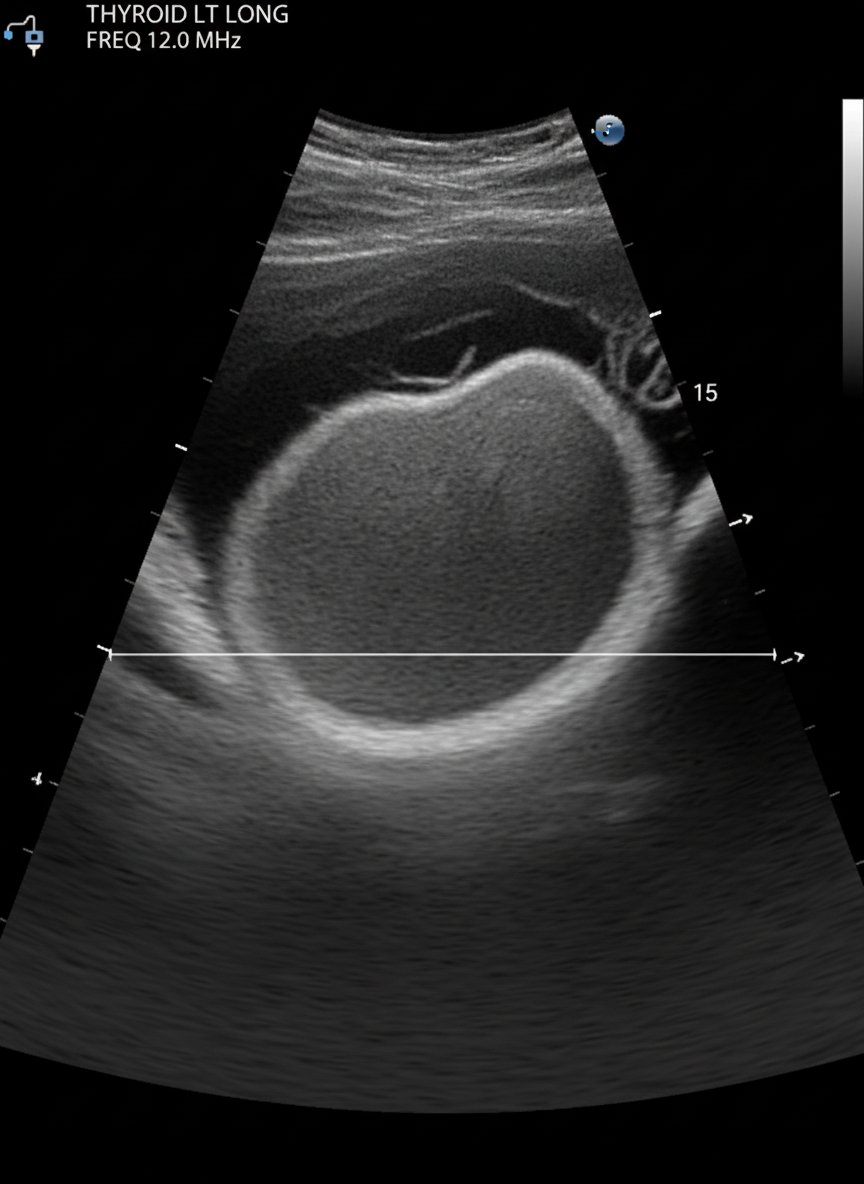

병원에 방문하면 보통 먼저 갑상선 초음파 검사를 하게 돼요.

이 검사는 통증 없이 빠르고 정확하게 갑상선의 상태와

결절의 유무, 크기, 모양 등을 확인할 수 있는 아주 유용한 방법이죠.